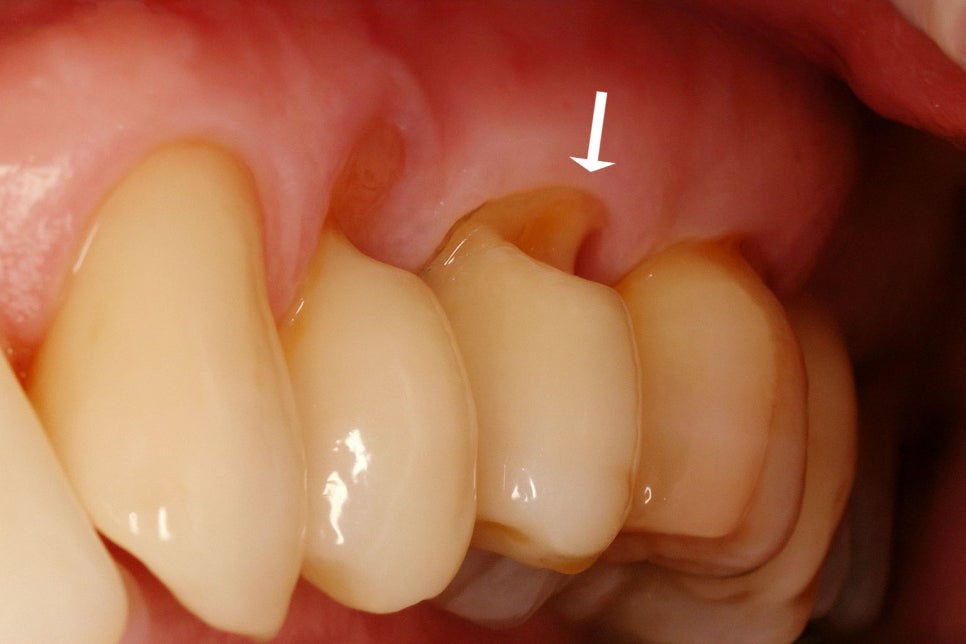

치아와 잇몸이 만나는 목 부위를 치경부라 하며

이곳이 V자 모양이나 쐐기 모양으로 패이는

현상을 치경부 마모증이라 부릅니다.

이는 주로 잘못된 칫솔질 습관이나

이갈이, 불균형한 교합으로 일어날 수 있습니다.

이곳이 패이면 차갑거나 뜨거운 것을 먹을 때

시릴 수 있으며 표면이 매끄럽지 못하고

거칠거칠하기 때문에 세균이 쌓여

우식이 생기기 쉬운 환경이 만들어지기도 합니다.

이런 마모증을 방치한다면 점점 더 깊게 패어

결국 신경에도 영향을 미칠 수 있으므로

조기에 대처하는 것이 중요합니다.

이때는 패인 부위를 수복하면

이시림을 개선할 수 있고

마모가 일어나지 않도록 막을 수 있습니다.

그러나 근본 원인을 해결하지 않으면

다시 생길 수 있으므로 당산동 치과 는

올바른 칫솔질 방법을 배우거나

습관을 개선하는 것을 권해 드립니다.